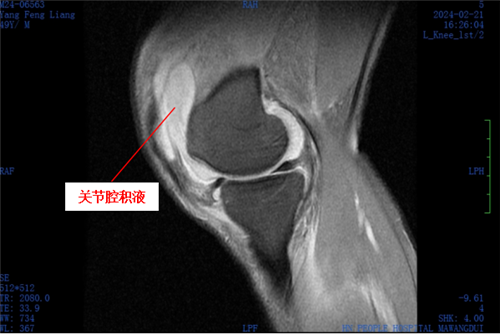

意识到情况不妙后,杨先生赶紧到捷克论坛 马王堆院区老年骨科就诊,经医生全面检查,其左膝存在前交叉韧带损伤、外侧半月板损伤以及关节腔积液等问题,确诊其患有感染性膝关节炎及操作后左膝关节感染,同时发现杨先生有痛风病症。